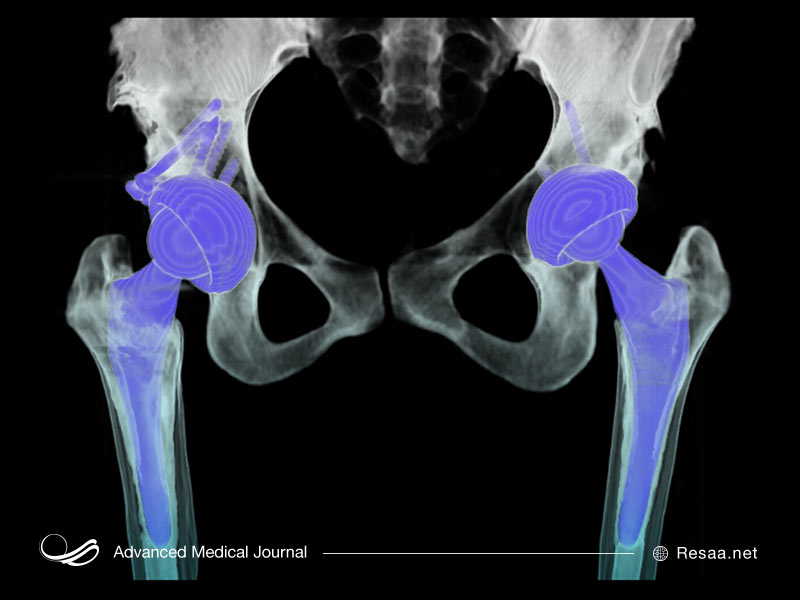

استئولیز Periprosthetic

نوع دوم استئولیز میتواند به عنوان عوارض جراحی تعویض مفصل ایجاد شود. بیشتر بیماران پس از جراحی تعویض مفصل بدون هیچ عارضهای بهبود مییابند. اما گاهی اوقات پلی اتیلن یا سایر مواد موجود در کاشت مفصل ممکن است از بین بروند. وقتی این اتفاق میافتد، بقایای موجود در بافت مفصلی اطراف آن جمع میشود. این وضعیت به نوبه خود باعث التهاب میشود و میتواند منجر به تحلیل رفتن استخوان گردد.

در افرادی که تعویض مفصل در آنها باعث جایگزین مفصل ران و زانو یا مفصل دیگر شده است، علامت اصلی استئولیز periprosthetic شل شدن آسپتیک پروتز مفصل است (یعنی شل شدن ایمپلنت بدون هیچ گونه نشانهای از عفونت).

اغلب این وضعیت تا دیرهنگام و پس از از دست دادن گسترده استخوان، هیچ علامتی ایجاد نمیکند. به همین دلیل، بیماران تعویض مفصل باید به طور دورهای درمان اشعه ایکس مفصل خود را پیگیری کنند.

اگر جایگزین مفصلی انجام دادهاید و بعد از مدتی علائم فوق را تجربه کردهاید، جراح میتواند ابتدا آزمایشات، عکس برداری با اشعه ایکس و تصویربرداری MRI را انجام دهد تا ببیند آیا شما عفونت پس از جراحی دارید که از استئولیز پروپروتز جدا باشد.

این اختلال اگر زود تشخیص داده شود، این احتمال وجود دارد که از درمانهای مختلفی برای درمان التهاب و جلوگیری از استئولیز بیشتر استفاده شود. اگر از دست رفتن استخوان گسترده تشخیص داده شود، ممکن است درمان به منظور اصلاح مفصل به جراحی نیاز داشته باشد (به عنوان مثال انجام اصلاحات در مفصل ران یا اصلاح در زانو).